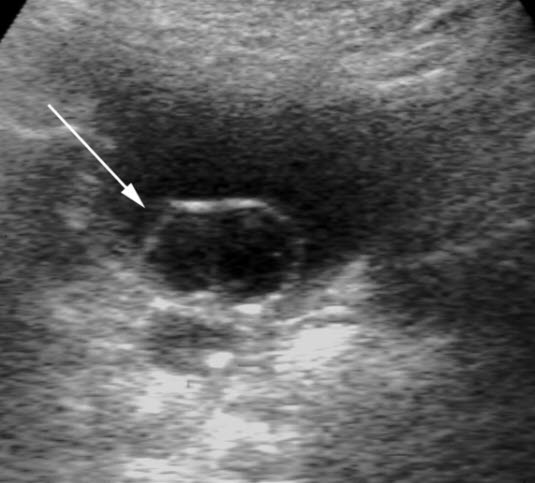

Ureterocele

Ureterocele (UL)

Ultralyd

Sekkformet utposning ved ureterostiet (pil)